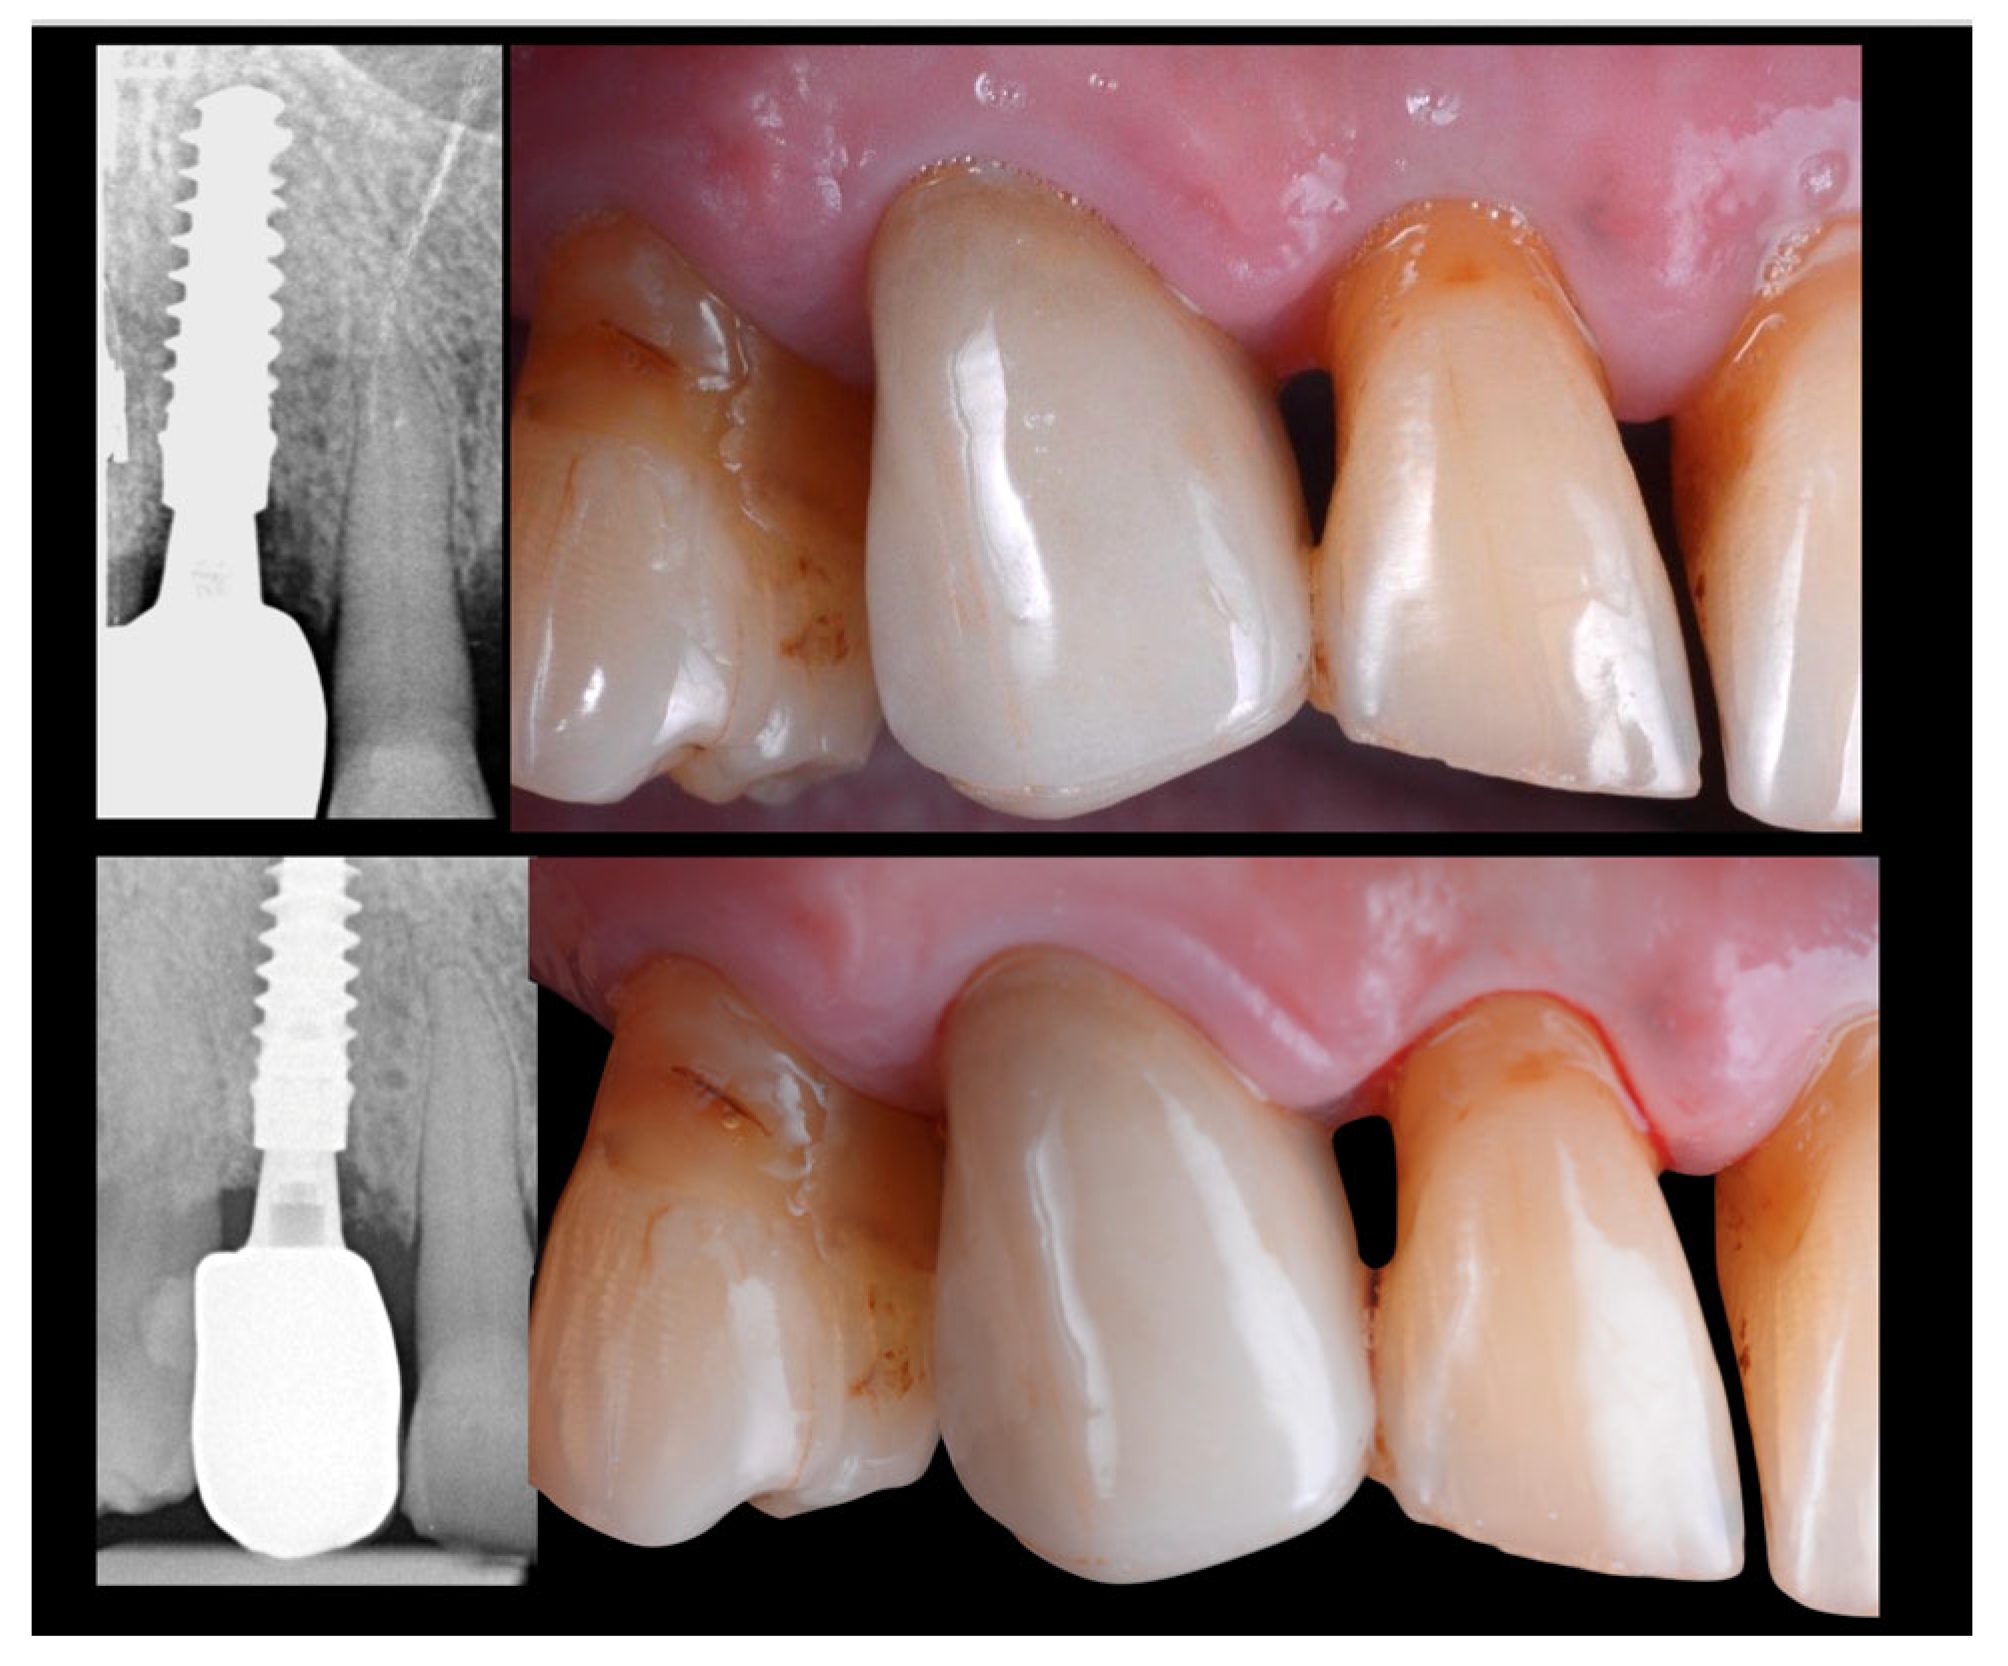

2.1. Case Presentation

2.2. Surgery